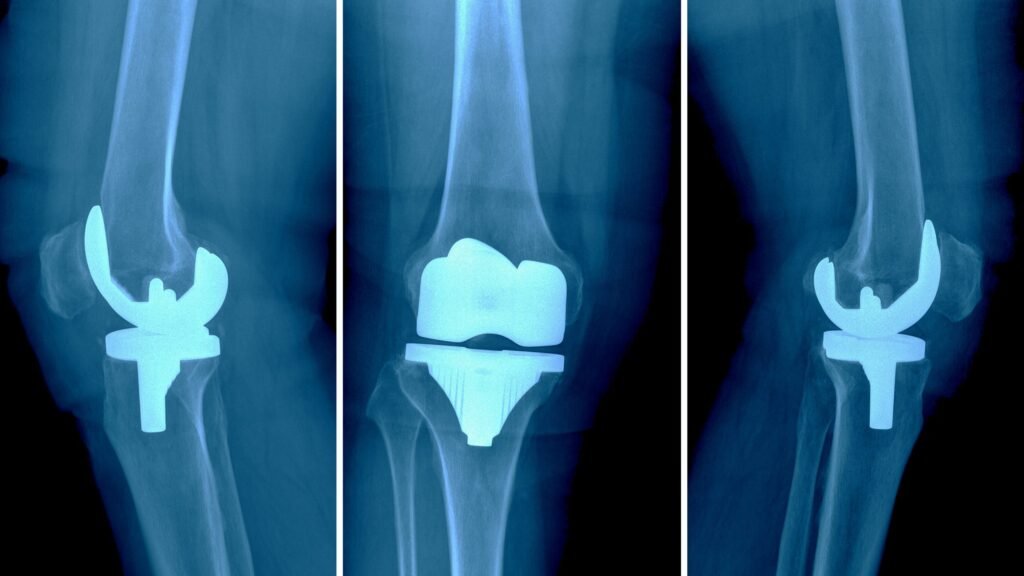

A painful or failed knee replacement occurs when the results of a total or partial knee replacement surgery are not satisfactory. This may involve ongoing pain, stiffness, instability, or a failure of the implant to function as intended.

In some cases, the implant may loosen, wear out, or become misaligned, leading to mechanical issues. In others, complications such as infection or scar tissue formation may contribute to pain and impaired function.